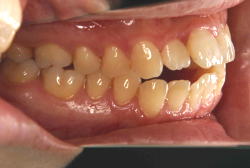

叢生(そうせい)

凸凹な歯並びのことを叢生といいます。矯正歯科に来院する患者様の主訴の中で、最も多いのが「配列の凸凹を真っ直ぐにしたい」というものです。歯の大きさと顎の大きさの調和がとれていないことが原因です。

凸凹を主体としたケースの場合、当院の平均治療期間は18ヶ月ですので、このケースは少し長めに経過しました。理由の一つは凸凹の程度がかなり重症だったと言うことですが、もう一つは、右下第2大臼歯が45度くらい前傾していたため、それを整直化させるために時間を要したと考えています。いずれにしても最終結果は大変よい状態と思います。

治療前は並びが乱れて見た目が悪いというのはもちろん問題ですが、歯科医学的に一番困るのは噛み合わせが悪いという点です。上下の犬歯(3番目の歯)は、上下的に離れた位置にあるため接触することができません。つまり歯としては存在していても、歯としては機能していないということです。